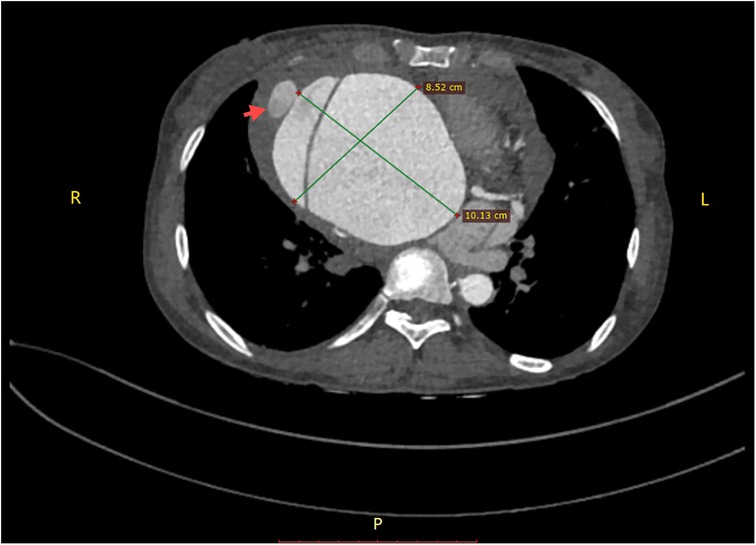

Figure 5

Pathological picture of the aneurysm wall (×400).

The surgical approach for this patient was the conventional method usually used by our team for second sternotomy surgery. However, some aspects are worth analyzing. One question is why the aneurysm grew so large in 20 years. Patients with some diseases, such as Marfan syndrome, vascular Ehlers-Danlos syndrome, Turner syndrome, and Loeys-Dietz syndrome, have a high risk of aneurysm expansion, dissection, and rupture (3, 4). The patient in this case had a congenital aortic developmental abnormality and had undergone surgical treatment. However, since the diameter of other blood vessels was normal (including at the site of the previous surgery), the ascending aortic tissue could have had a congenital developmental abnormality. Our pathology report also indicated that the ascending aortic wall had fibrous connective tissue hyperplasia and lacked normal elastic fiber tissue (Figure 5). During surgery, we found that the patient's previous surgical incision had shifted to the posterior wall of the aneurysm (Figure 3A), indicating that the enlargement of such a large aneurysm may be asymmetric, not coaxial, and is the first time this phenomenon was observed in such patients. The fact that such a large aneurysm grew in such a slender patient without rupture may be related to the patient's previous cardiac surgery, in which adhesions formed around the aorta, preventing acute rupture (5, 6).